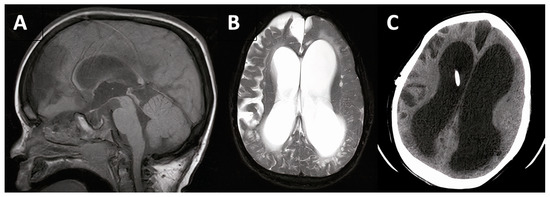

3.1.1. Case #1. Hydrocephalus with Chiari I Malformation

| 1 | 6 y, F |

|